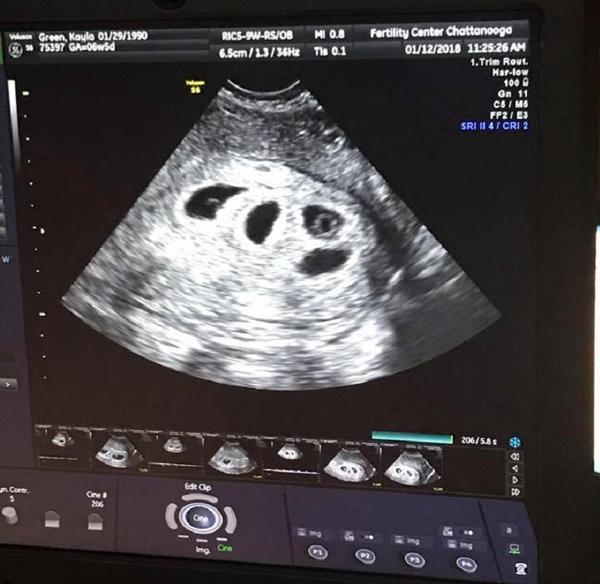

Khi Kayla đi siêu âm thai 6 tuần, bác sĩ đã thông báo tin sốc. Cô đang mang thai không phải 1 mà tới 4 đứa trẻ.

Trong buổi siêu âm tuần thứ 6, Kayla được biết mình đang mang thai tới 4 đứa trẻ.